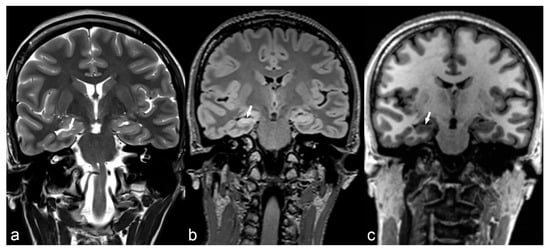

Classical lissencephaly is characterized by reduced or absent gyri associated with a thickened cortex and shallow sulci. Microscopically, the cortex lacks the normal lamination and consists of only 4 layers instead of the typical 6 layers. Macroscopically, the sylvian and Rolandic fissures are poorly developed and there is a failure of operculization of the insular areas [85]. This results in a smooth appearance of the brain surface with the characteristic “Figure 8” or “hourglass” shape of the brain in axial images (Figure 6) [83]. There are several gene mutations implicated in its pathogenesis and a wide spectrum of clinical manifestations such as severe intellectual disability, hypotonia and epilepsy. It is usually diagnosed early in life, although mild cases may have delayed presentation [69]. Miller-Dieker syndrome (MDS) is a severe form of classical lissencephaly associated with facial dysmorphism and occasionally other congenital abnormalities, epilepsy and a severely shortened life expectancy, related to a chromosome 17 gene deletion. Cobblestone lissencephaly is a distinct form of lissencephaly characterized by a nodular appearance of the brain cortex secondary to abnormal organization of the cortical layers.

Figure 6.

6-month-old baby. Axial T2WI slices through the lateral ventricles (a) and occipital lobes (b) demonstrate a distinct lack of normal brain gyration with a smooth and thickened appearance of the cortex and unfolded gyri, most pronounced in both parietal, temporal and occipital lobes (arrows) consistent with lissencephaly. Note the posterior-anterior gradient with some rudimental sulcation seen in the frontal lobes. Band heterotopia can be clearly seen in the parietal regions on sagittal T1 IR (c) with cobblestone appearance (arrow).